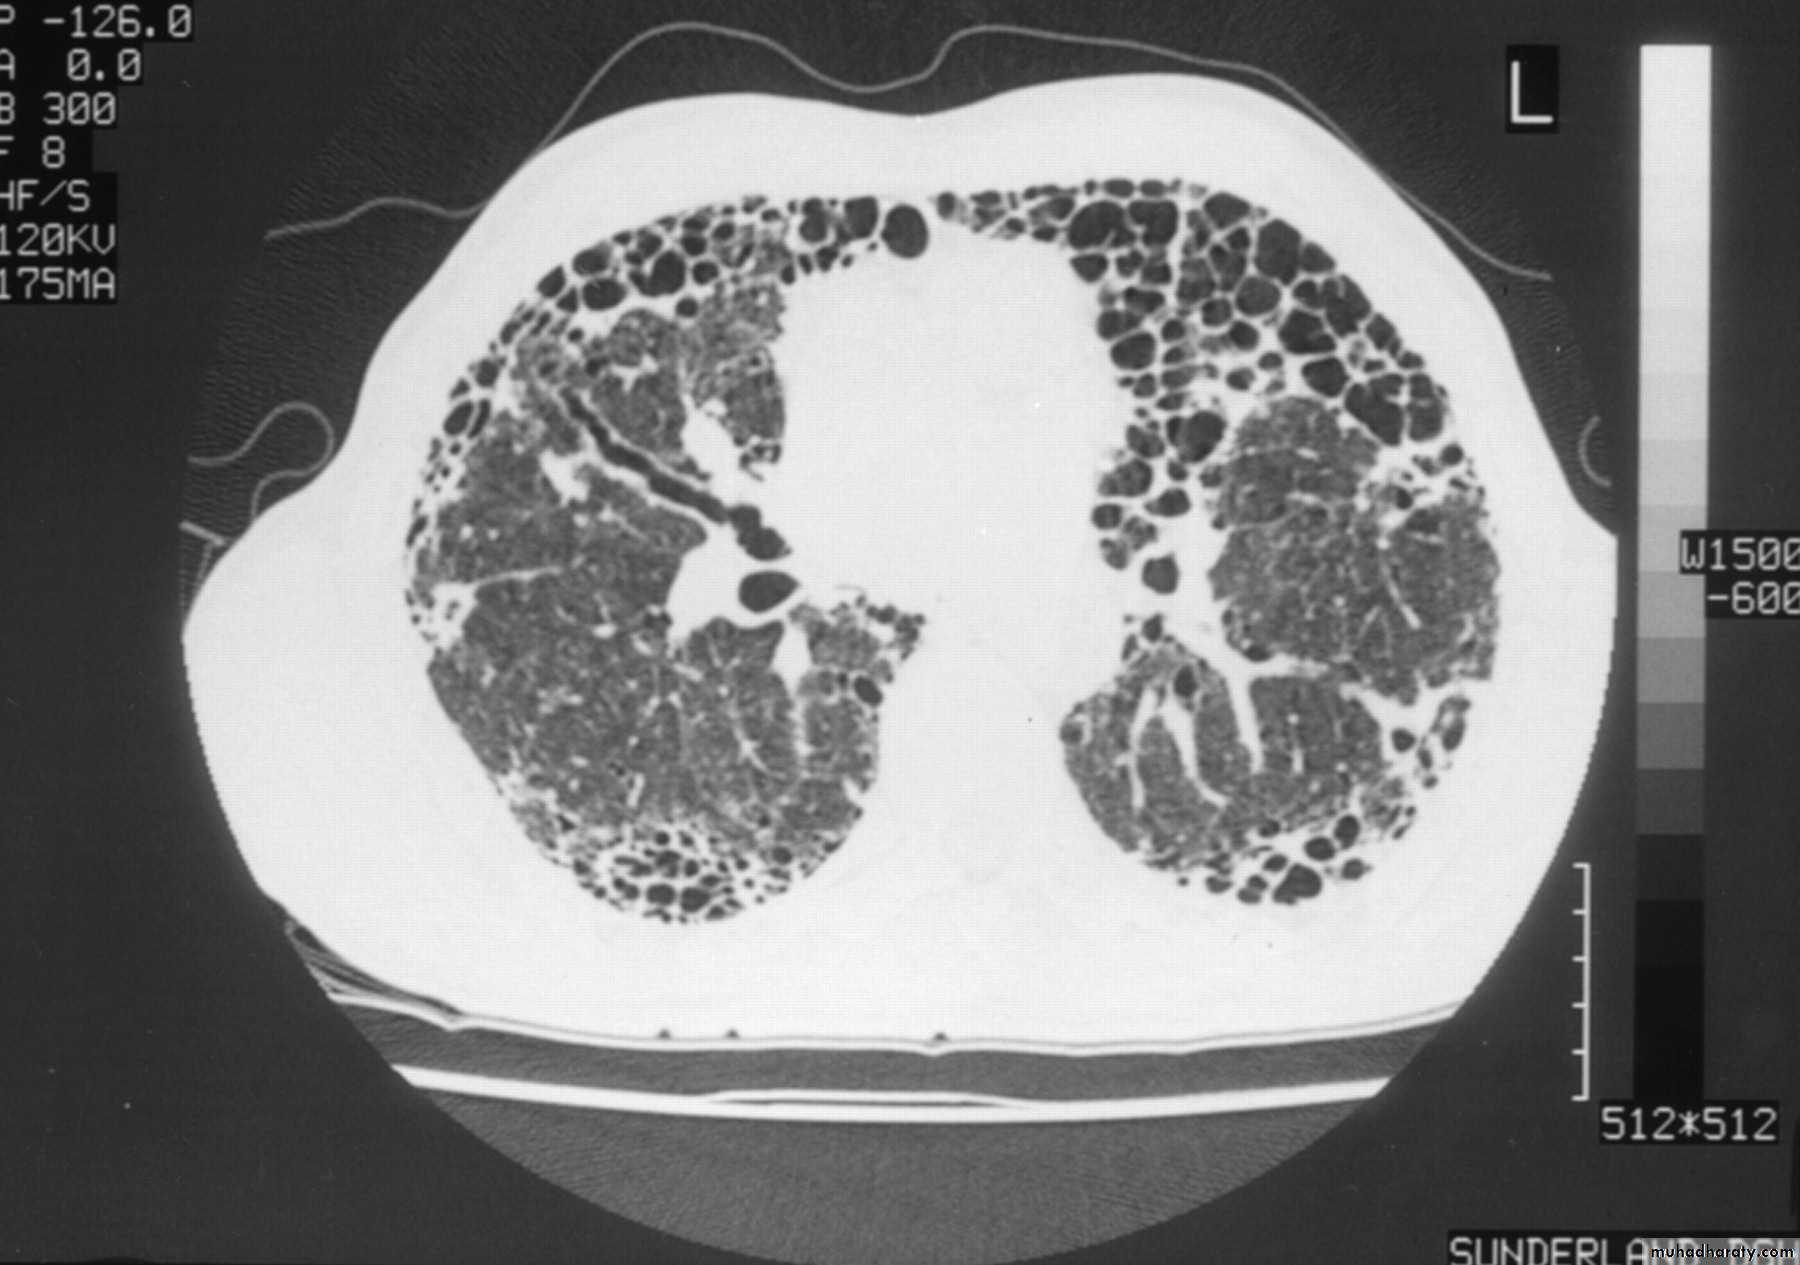

Chest X-ray -irregular reticulonodular shadowing (often maximal in the lower zones) and finally a honeycomb lung■ High-resolution CT scan (HRCT) shows characteristic features (diagnostic accuracy of approximately 90%).

■ pulmonary function tests show a restrictive ventilatory defect ,the lung volumes are reduced, the FEV1 to FVC ratio is normal to high and carbon monoxide gas transfer is reduced.

@$The chest X-ray shows bi-basal reticulonodular shadowing and honeycombing may be present.@HRCT is more sensitive .